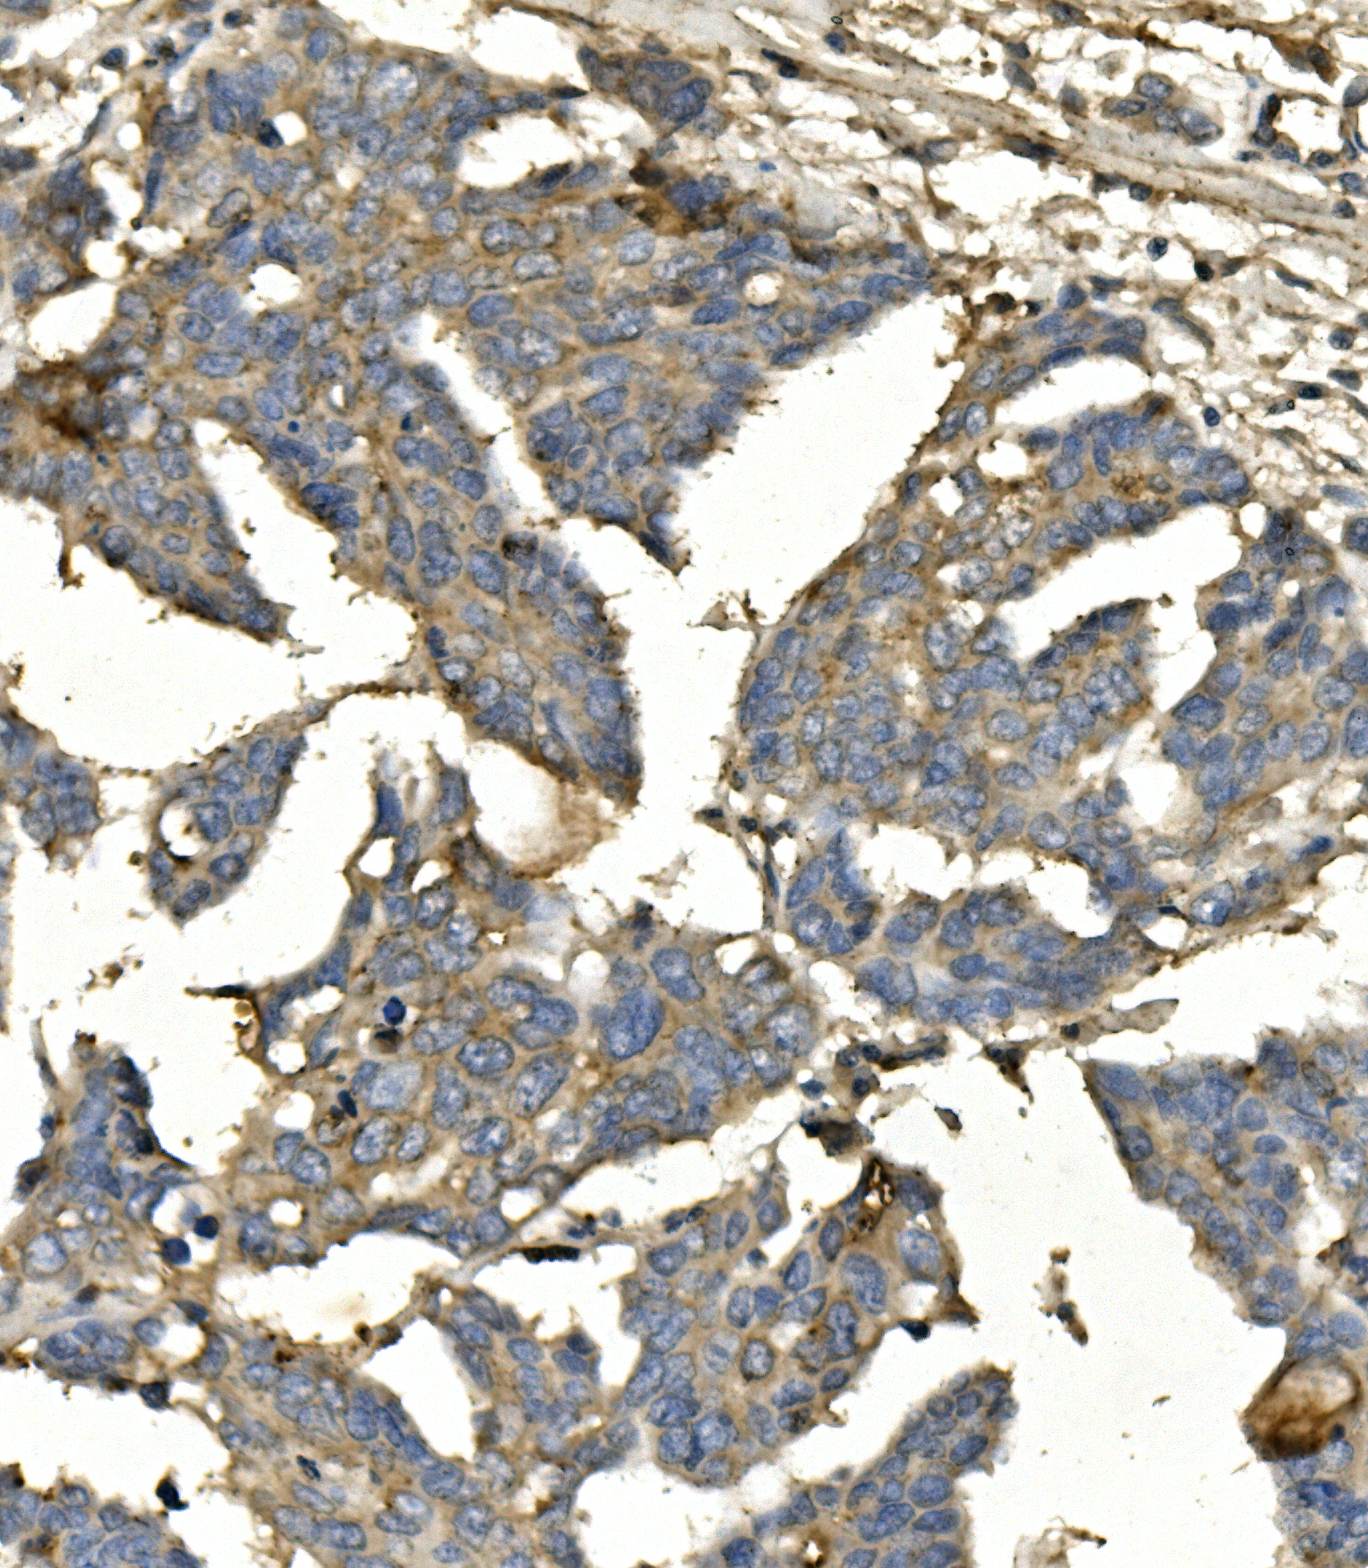

IHC analysis of BubR1/BUB1B using anti-BubR1/BUB1B antibody (M01564-2).

BubR1/BUB1B was detected in a paraffin-embedded section of human Ovarian cancer tissue. Biotinylated goat anti-mouse IgG was used as secondary antibody. The tissue section was incubated with mouse anti-BubR1/BUB1B Antibody (M01564-2) at a dilution of 1:200 and developed using Strepavidin-Biotin-Complex (SABC) (Catalog # SA1021) with DAB (Catalog # AR1027) as the chromogen.